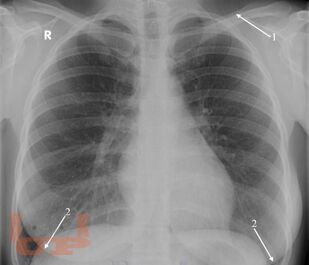

Рентгеноанатомия органов грудной клетки

Губик Е. А. Рентгеноанатомия органов грудной клетки : Учебное пособие / Е. А. Губик, Т. В. Кузина. - Чита : Издательство ЧГМА, 2023. - 76 c. - Текст : электронный // ЭБС "Букап" : [сайт]. - URL : https://www.books-up.ru/ru/book/rentgenoanatomiya-organov-grudnoj-kletki-16748814/ (дата обращения: 26.05.2026). - Режим доступа : по подписке.

В данном электронном пособии систематизированы и подробно изложены сведения о рентгеновской анатомии органов грудной клетки.